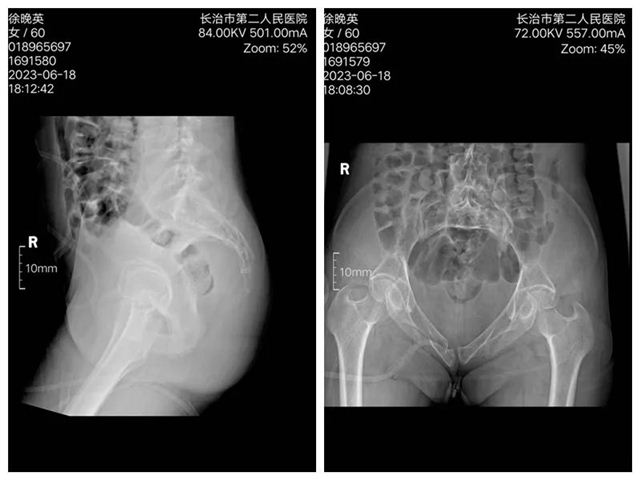

近日,长治二院创伤骨科二病区在智能骨科手术机器人辅助下,成功为两位骶骨、耻骨骨折患者实施手术。 病 例 一 术前影像 入院后,李黎明主任团队综合评估病情,为充分减少创伤,更加利于患者术后康复,决定应用更加先进、更加精准的骨科手术机器人辅助下的微创技术,为徐某行机器人辅助下骨盆骨折闭合复位内固定术。 手术过程中,李黎明主任,徐彦芳医生通过调整透视定位后将骨盆透视影像导入机器人操作界面,在该界面,根据扫描影像规划骶髂螺钉置入位置、方向、长度等数值,在导航系统引导下,经皮小切口精准置入S1,S2通道螺纹导针。经C型臂透视后证实骨折复位满意,导针位置好后,拧入规划长度的螺钉。 术后影像 病例二 术前影像 术后影像 骨科创伤二病区李黎明主任表示,智能骨科手术机器人集合了人工智能、精准手术、安全微创等特色,优势明显。特别是遇到复杂疑难的手术时,利用影像学精准建模,经过术前规划确定骨折位置,明确置入位置和角度,在术中利用灵活的机械臂进行实时定位图像导航,确保螺钉的实际置入零误差,大大降低了术中的风险。 据了解,自2021年10月“天玑”骨科手术机器人投入使用以来,我院骨科共为76名,骨折、骨伤患者成功实施了手术。